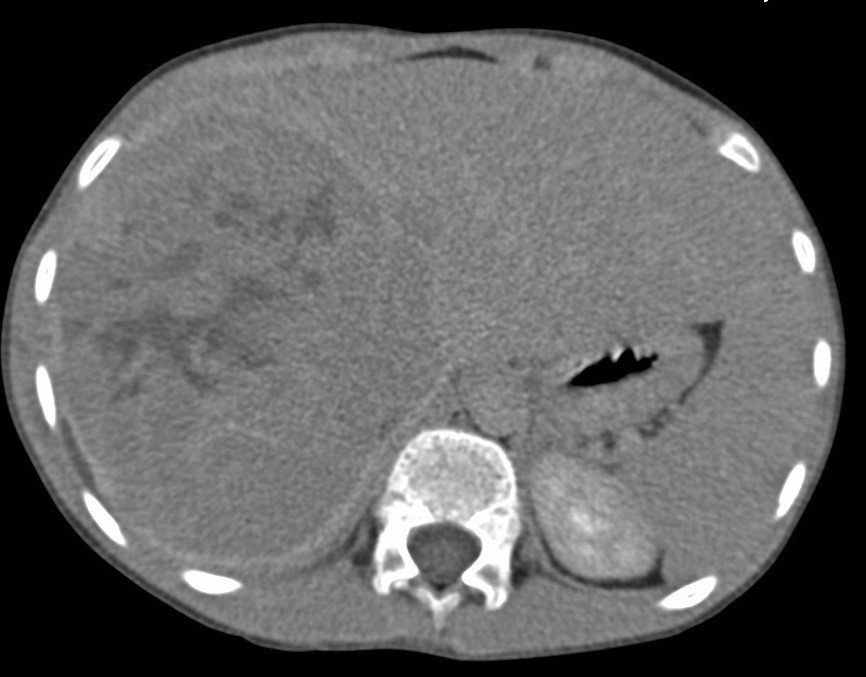

• Kolorektal metastazların spesifik diaqnostik əlaməti yoxdur, diaqnoz kriteriyalara və differensiasiyaya əsasən qoyulur.

• Görüntüləmə üsulları diaqnozun dəqiqləşdirilməsində və mərhələnin təyinində önəmlidir.

• CEA artması diaqnozu dəstəkləyir, artmaması isə inkar etmir.

• Biopsiya differensial diaqnostika çətinliyi olarsa tətbiq edilir.

Diaqnostik kriteriyaları:

• Hazırda və anamnezdə kolorektal xərçəng.

• Görüntüləmədə bədxassəli şişlərə məxsus kontrastlaşma (arterial fazada periferik kontrastlaşma, venoz fazada yuyulma).

• Biopsiyada adenokarsinoma metastazı.